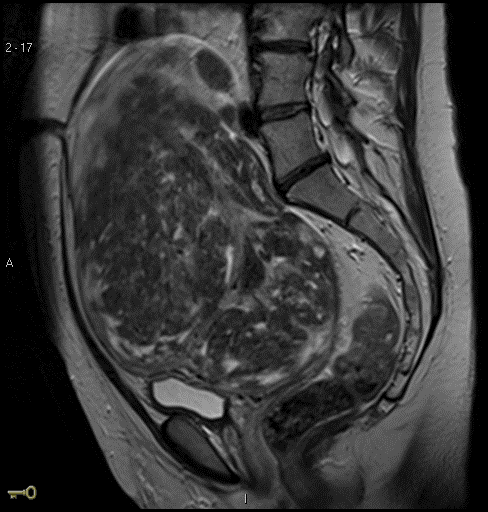

What abnormality is shown in this MRI ?

Uterine fibroid